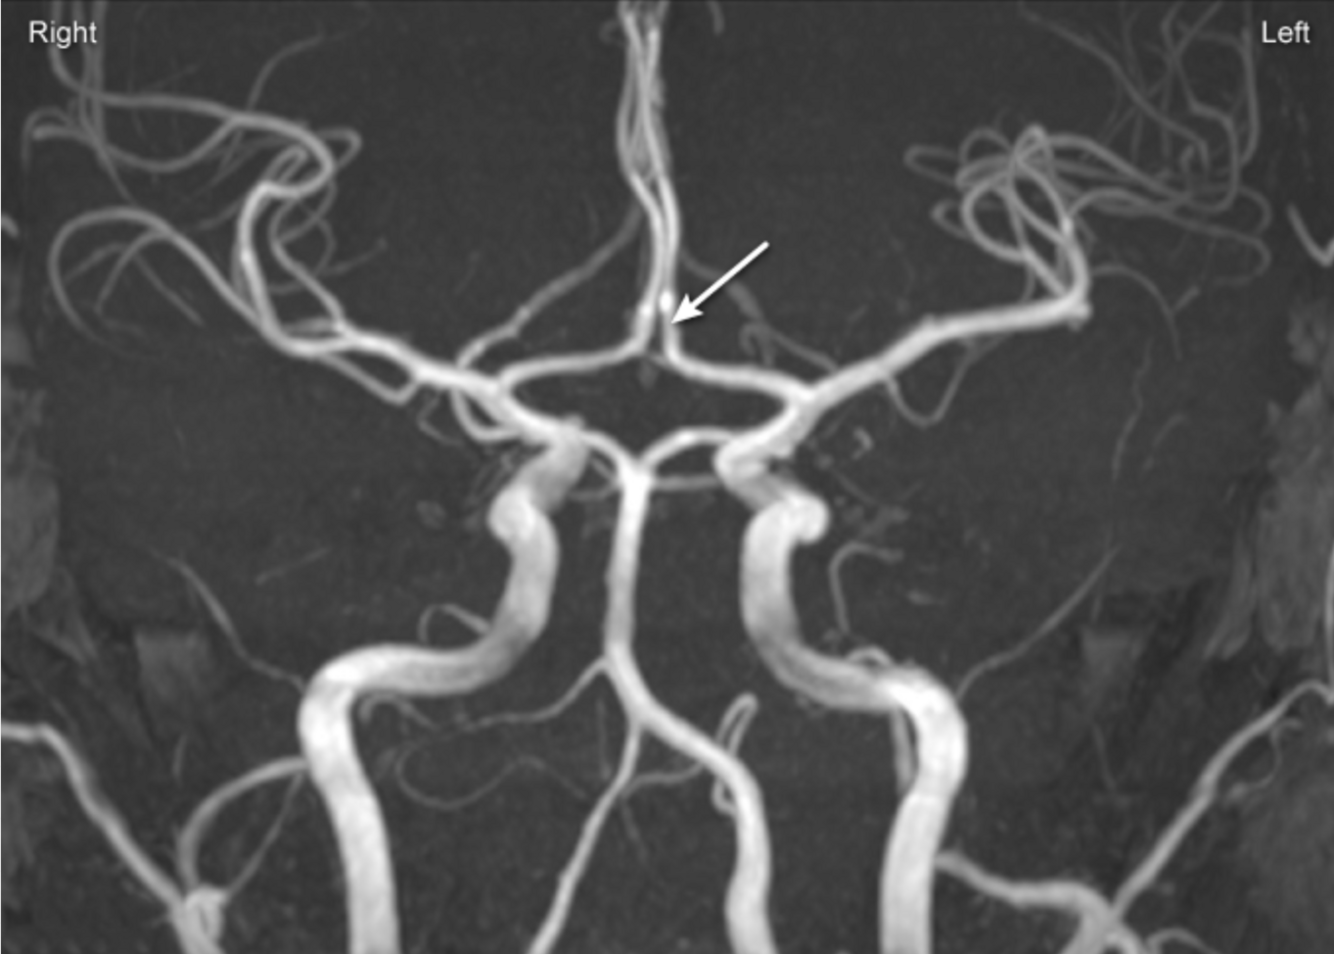

Selon l’image suivante, quelle artère semble être atteinte chez ce patient ?

a. A

b. B

c. C

d. D

e. E

A

c. C (artère cérébrale moyenne droite)

Considérant que la faiblesse est à gauche, nous savons que l’atteinte est du côté droit. Cela se confirme par l’orientation des yeux du côté droit (Right-way eyes), ainsi que par la présence d’héminégligence. Puis, considérant que l’atteinte est à prédominance brachio-faciale, l’artère cérébrale moyenne semble atteinte.

Un doppler de la carotide est effectué et il démontre une sténose de 85%. Vous effectuez ensuite une angiographie avec pose de tuteur, mais lors de la procédure, un embole se détache et vient obstruer l’artère identifiée sur l’image suivante.

Parmi les actions suivantes, laquelle sera impactée chez ce patient secondairement à l’embolisation ?

a. Monter les escaliers

b. Serrer le poing

c. Parler

d. Déglutir

e. Siffler

En effet, l’artère cérébrale antérieure irrigue entre-autres la zone inter-hémisphérique et par le fait même, elle est responsable d’irriguer la zone responsable du contrôle moteur des membres inférieurs.